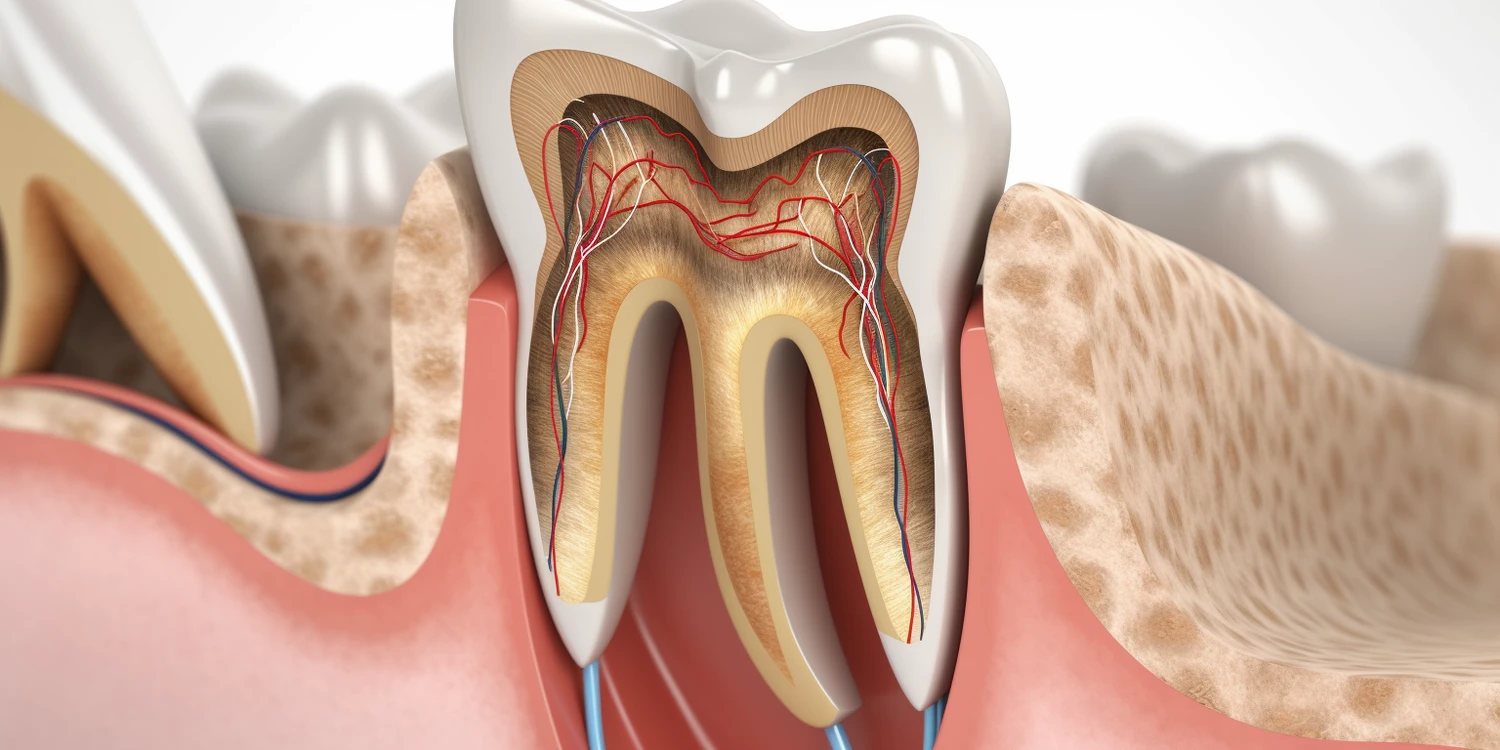

Palacze często doświadczają szeregu zmian w jamie ustnej, które mogą być dostrzegane przez dentystów podczas wizyt kontrolnych. Jednym z najczęstszych objawów jest przebarwienie zębów, które może przybierać żółty lub brązowy odcień w wyniku osadzania się substancji smolistych i nikotyny. Dodatkowo palacze są bardziej narażeni na rozwój chorób dziąseł, takich jak zapalenie dziąseł czy paradontoza, co może prowadzić do utraty zębów. Zmiany te są wynikiem osłabienia układu odpornościowego oraz zmniejszenia przepływu krwi do tkanek jamy ustnej. Ponadto palacze mogą doświadczać suchości w ustach, co sprzyja powstawaniu próchnicy i innych problemów stomatologicznych. Dentyści mogą również zauważyć obecność owrzodzeń lub zmian nowotworowych w jamie ustnej u osób palących, co stanowi poważne zagrożenie dla zdrowia.

Palenie papierosów ma istotny wpływ na proces leczenia stomatologicznego, co powinno być brane pod uwagę przez pacjentów oraz dentystów. Osoby palące mogą doświadczać opóźnionego gojenia się ran po zabiegach chirurgicznych w jamie ustnej, takich jak ekstrakcje zębów czy implantacje. Nikotyna i inne substancje chemiczne zawarte w papierosach ograniczają przepływ krwi do tkanek, co utrudnia regenerację i może prowadzić do powikłań. Dodatkowo palacze są bardziej narażeni na infekcje po zabiegach stomatologicznych, co może skutkować koniecznością dodatkowego leczenia. W przypadku osób planujących zabiegi takie jak implanty zębowe, dentyści często zalecają rzucenie palenia na kilka tygodni przed i po zabiegu, aby zwiększyć szanse na sukces procedury. Ponadto palacze mogą wymagać częstszych wizyt kontrolnych oraz dodatkowych zabiegów profilaktycznych, aby utrzymać zdrowie jamy ustnej na odpowiednim poziomie.

Długoterminowe skutki palenia papierosów dla zdrowia jamy ustnej są niezwykle poważne i mogą prowadzić do wielu problemów stomatologicznych. Przede wszystkim palacze są znacznie bardziej narażeni na rozwój nowotworów jamy ustnej, w tym raka języka, warg oraz gardła. Palenie wpływa również na stan dziąseł, prowadząc do przewlekłego zapalenia dziąseł oraz paradontozy, które mogą skutkować utratą zębów. Dodatkowo osoby palące często borykają się z suchością w ustach, co sprzyja rozwojowi próchnicy oraz innych chorób jamy ustnej. Zmiany te mogą być trudne do odwrócenia, a ich konsekwencje mogą wpłynąć na jakość życia pacjenta. Warto również zauważyć, że palacze często mają gorszą higienę jamy ustnej, co dodatkowo pogarsza ich stan zdrowia.